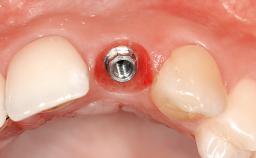

In September 2004, a 38-year-old female patient, a nonsmoker, was referred to our clinic for the replacement of the missing left central maxillary incisor (tooth 21),which had been removed two months before the initial appointment due to a vertical root fracture. The dental patient history revealed that the tooth in question had supported a ceramo-metal crown for more than ten years before the root fracture occurred. Implant therapy (single-tooth replacement) was considered the first therapeutic choice, as the neighboring teeth did not require significant restoration. The patient was in good general health, and her medical history revealed no significant findings.